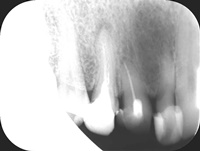

Trzykanałowa górna czwórka, nieczęsty przypadek.

Pacjentka zgłosiła się z bólem. Ząb prawa dolna czwórka po leczeniu kanałowym. Nawracające dolegliwości bólowe, od kilku lat okresowo zaostrzające się. Podjęto decyzję o rewizji leczenia kanałowego. Udróżniono kanał korzeniowy, oraz odnaleziono kanał dodatkowy. Zdjęcie początkowe i zdjęcie po leczeniu endodontycznym pod mikroskopem.